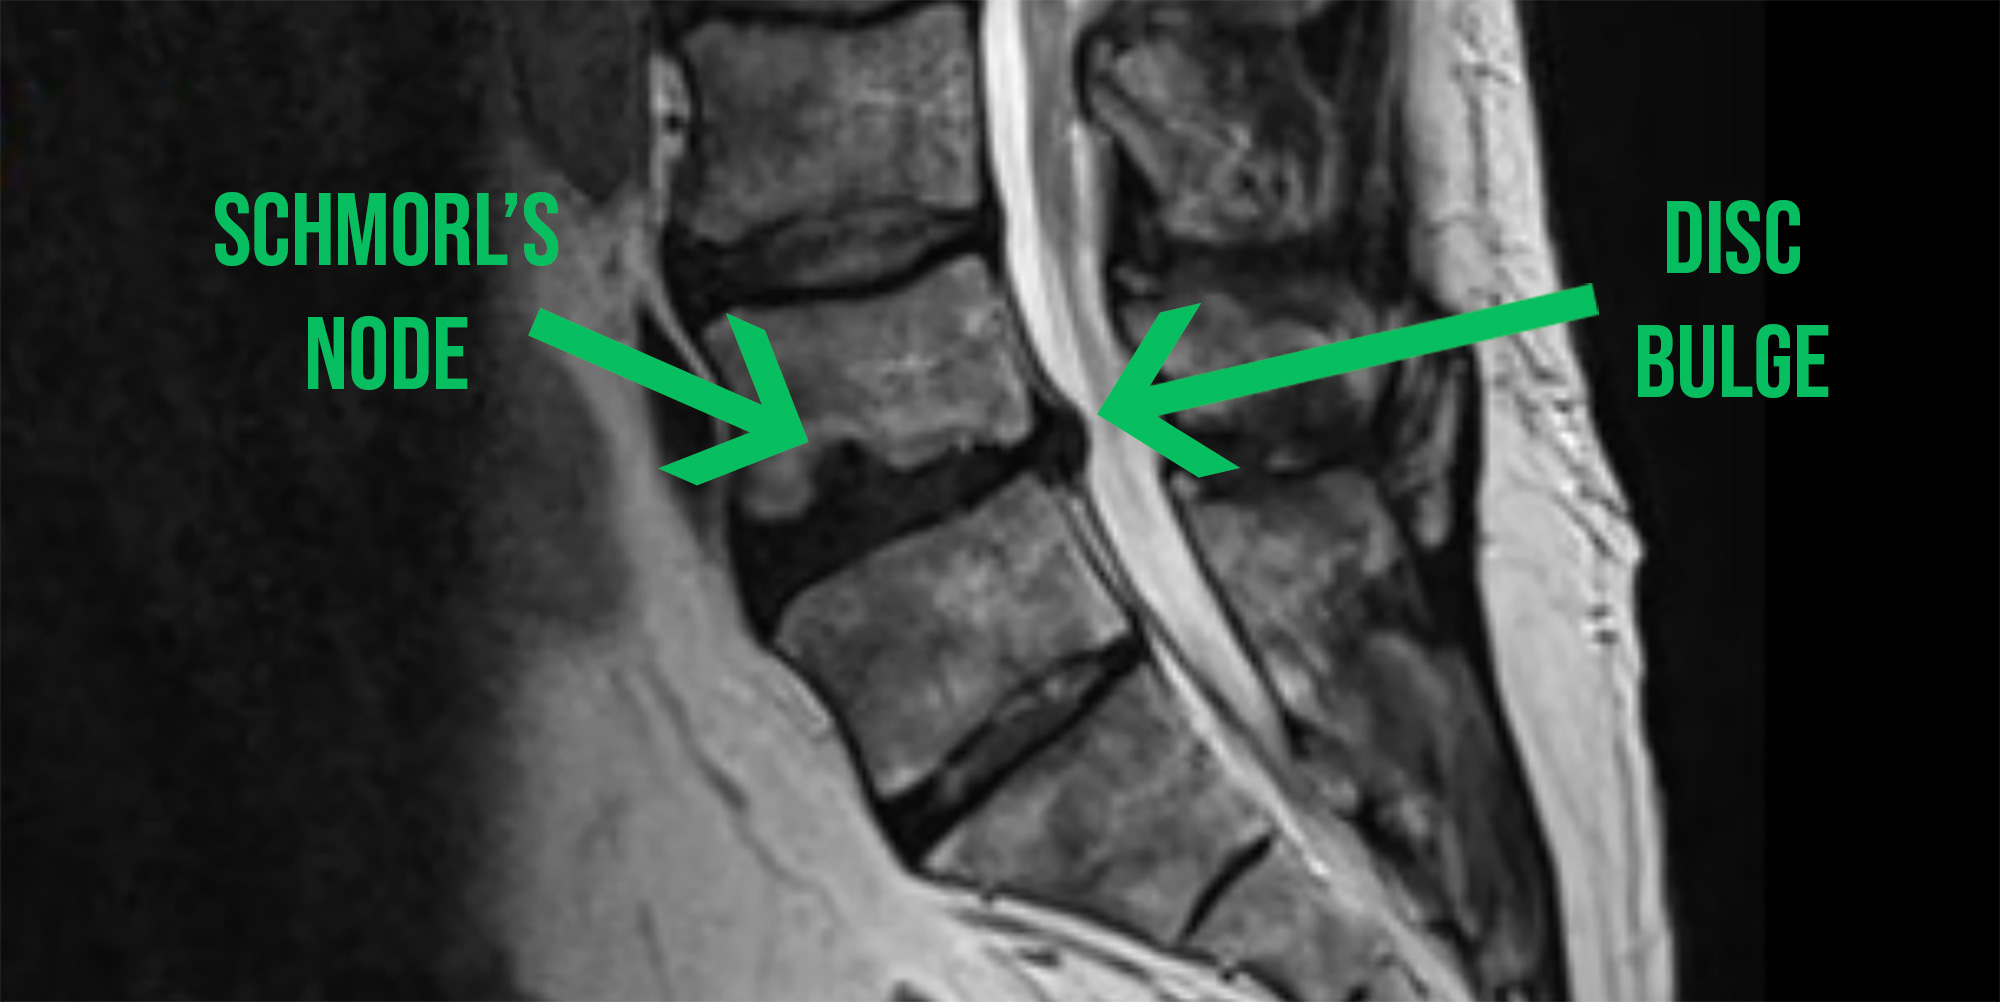

In young, healthy spines, the first part of the disc to get damaged is often the end plate (the superior or inferior interface of the disc with the vertebra which has a thickness of about half a millimetre). This occurs due to rapid compressive forces that occur in weightlifting, or in Ali's preferred sport, MMA.

This allows some of the nucleus of the disc to migrate into the vertebra above or below the disc (forming a Schmorl’s node), causing the joint to lose some of it's rigidity which alters the mechanics of the joint.

The resulting loss of joint stiffness can then lead to further damage of the passive joint tissues (discs and ligaments) which can result in a disc bulge or herniation.

The facet joints are the small joints at the back of the spine. As disc mechanics change, those joints start to take more compressive stress and can develop arthritic changes over time (arthropathy). This is what was visible on Ali's recent MRI.